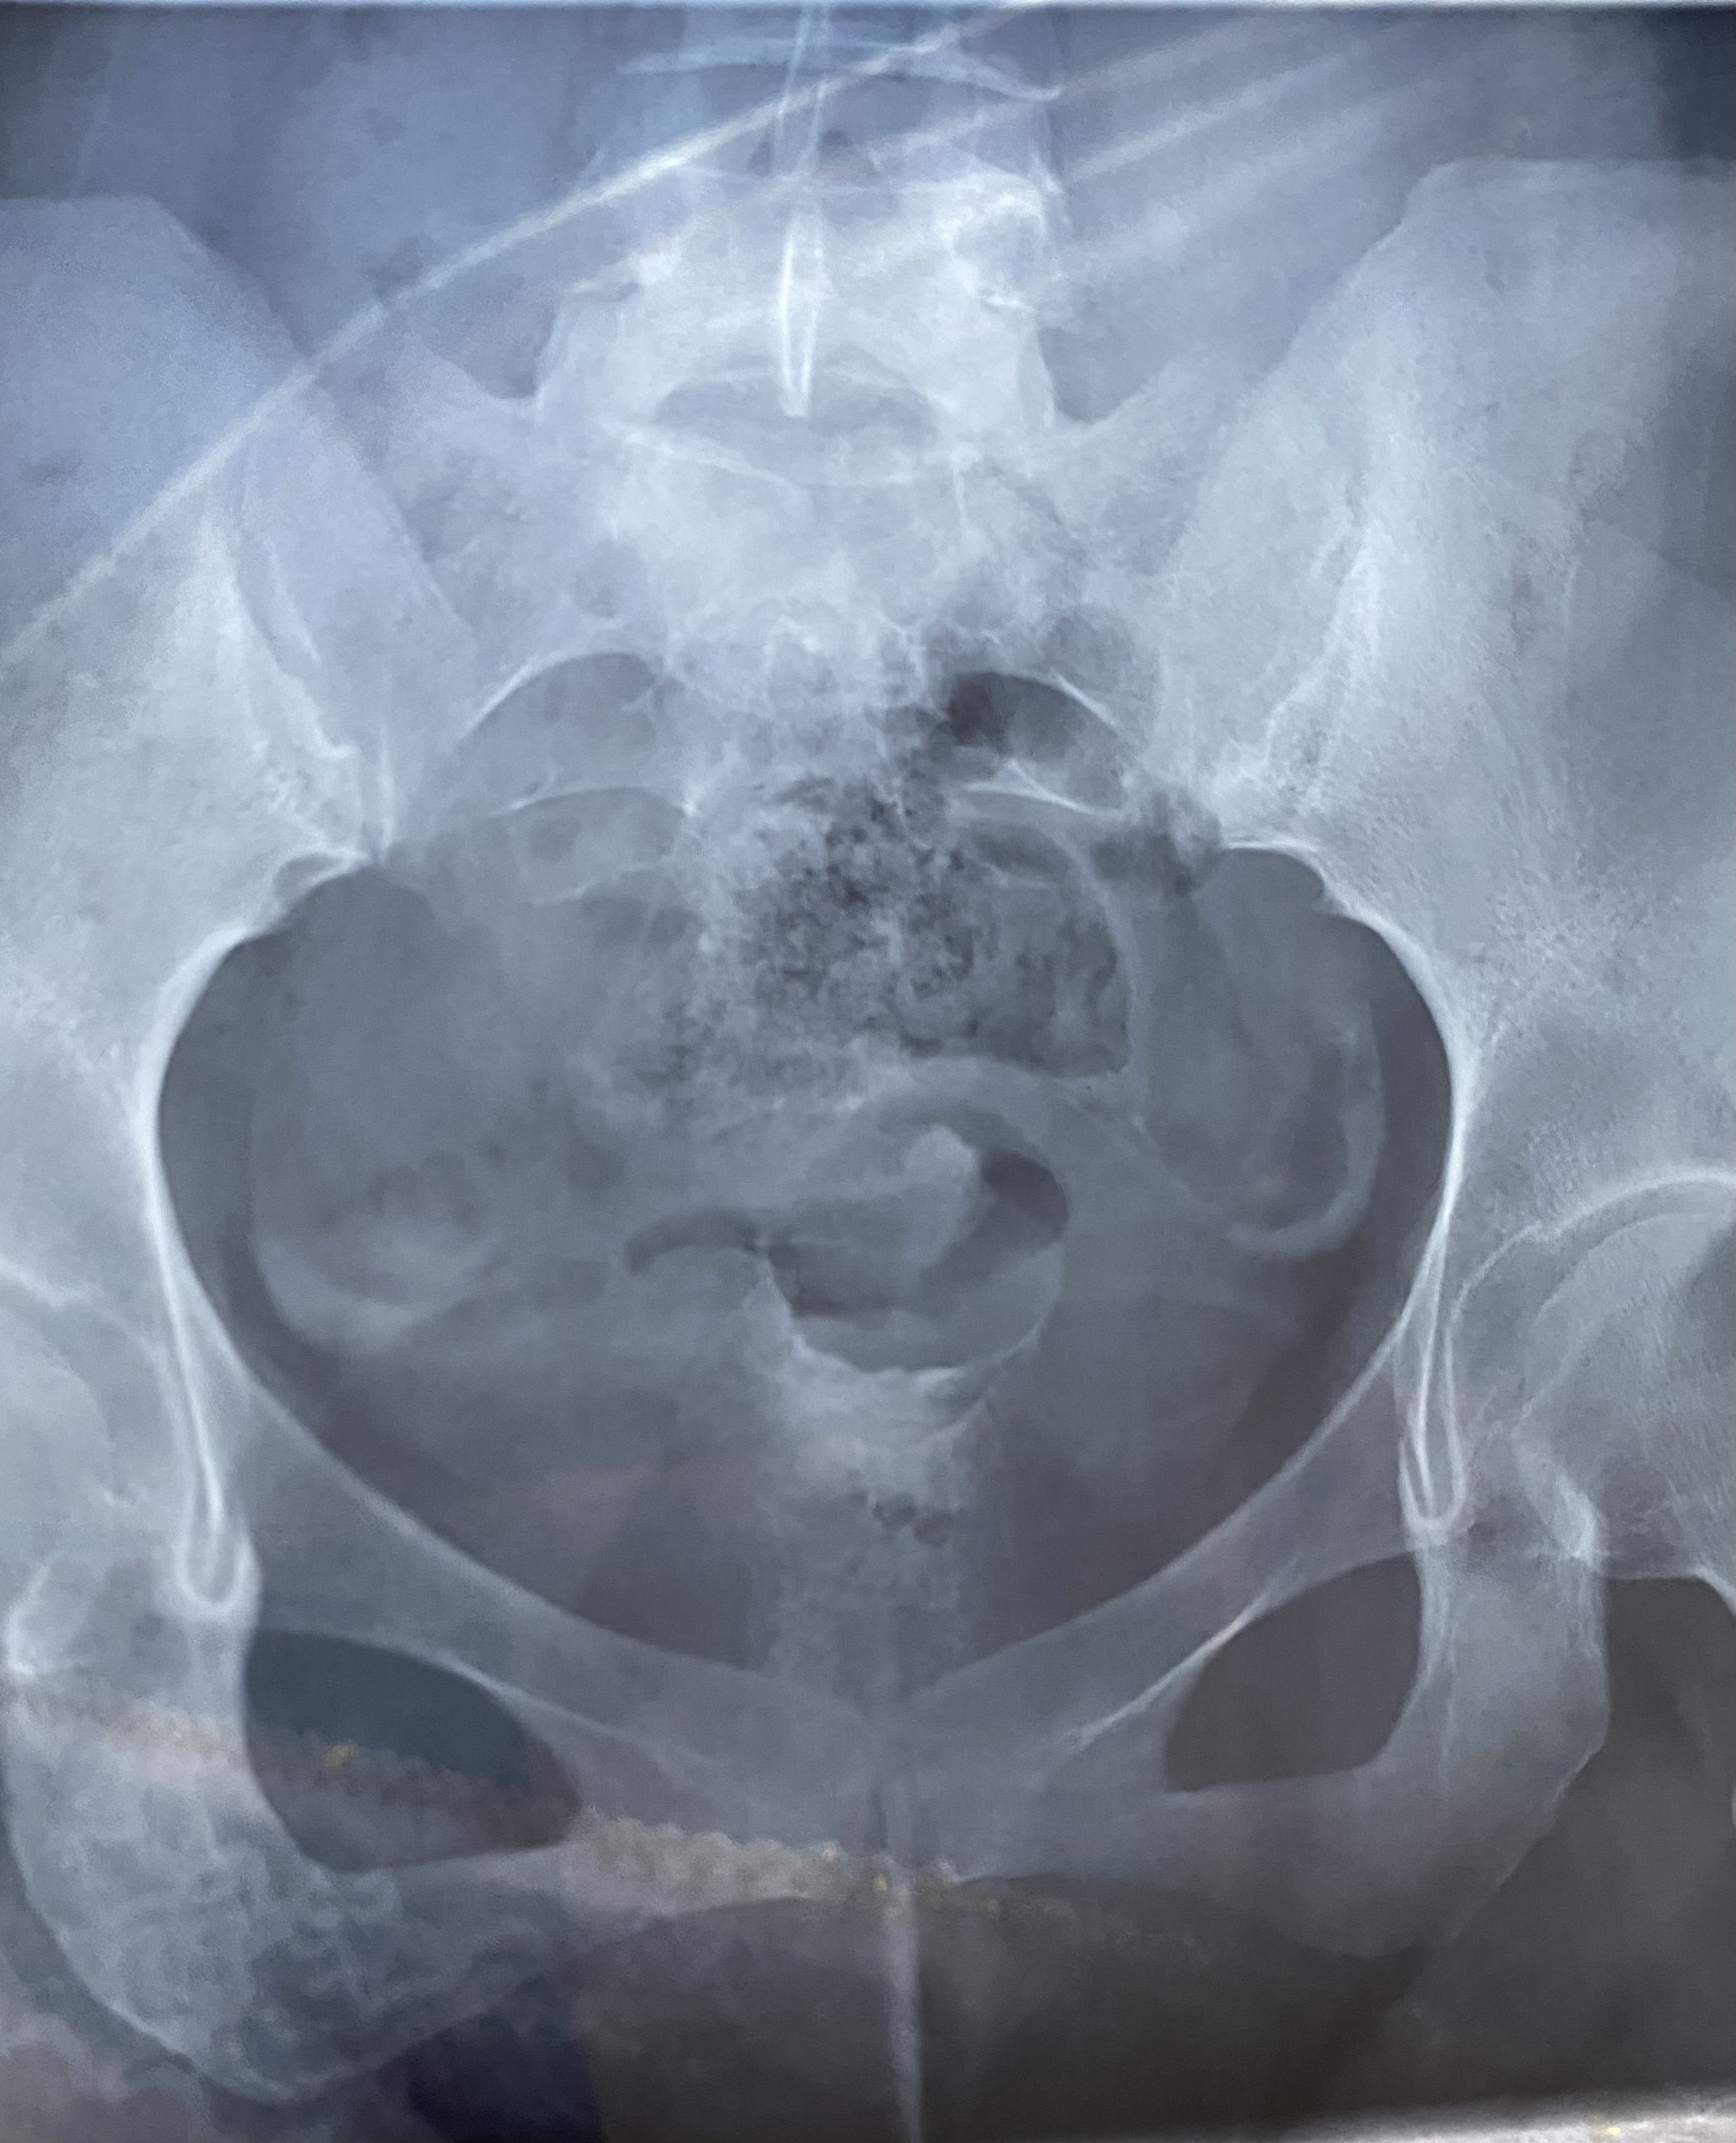

医生您好,帮我看看输卵管报告,报告上虽然没有异常,但片子看着左侧有点上举,这样影响怀孕吗?另外我b超显示宫腔中段有子宫内膜息肉0.5×0.3备孕快一年了没怀孕,我不孕的原因是因为息肉还是也和输卵管有点关系?

上举点不影响怀孕的,内膜息肉不大,但一年不怀孕,应该把息肉切除,有的切除息肉就可以怀孕的,同时男方查精液常规。